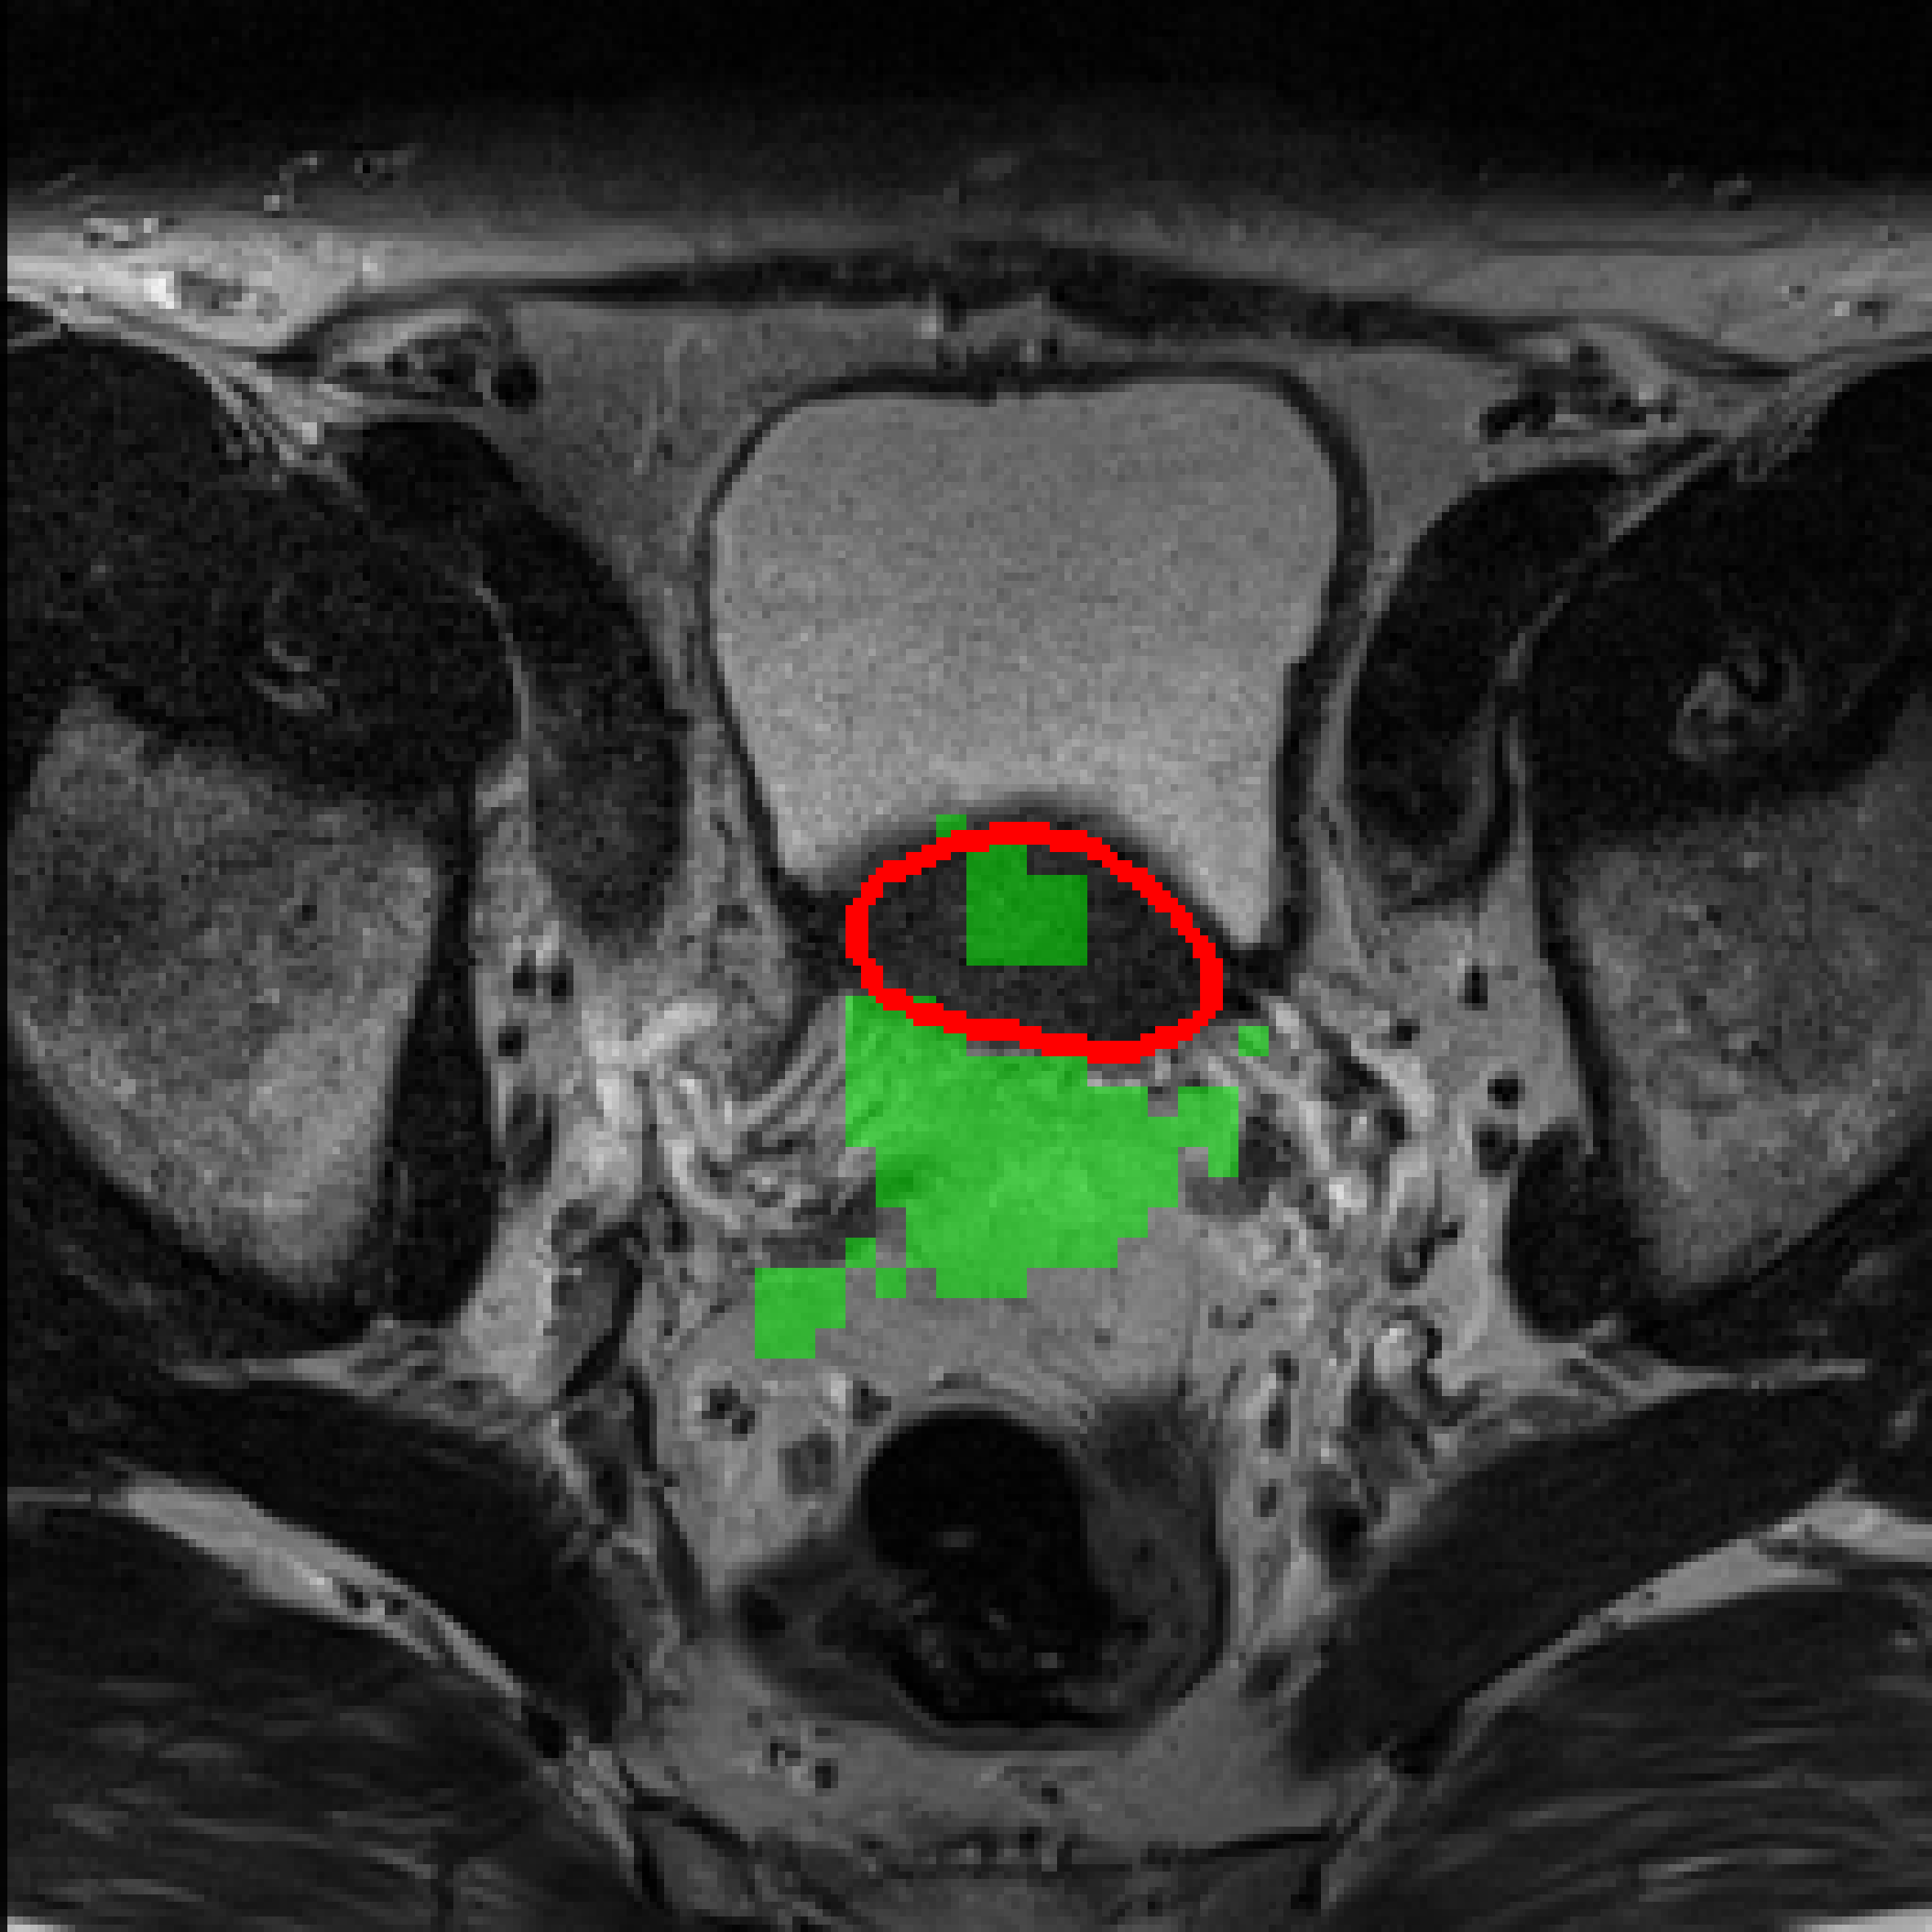

3.3 Qualitative results

Table 3: Qualitative results of different methods, \Circle and \CIRCLE denote groundtruth and predicted mask, respectively.

SAM MedSAM SAM-Med2D CPC-SAM KnowSAM Ours

5% Promise [Uncaptioned image] [Uncaptioned image] [Uncaptioned image] [Uncaptioned image] [Uncaptioned image] [Uncaptioned image]

10% Promise [Uncaptioned image] [Uncaptioned image] [Uncaptioned image] [Uncaptioned image] [Uncaptioned image] [Uncaptioned image]

5% Colon [Uncaptioned image] [Uncaptioned image] [Uncaptioned image] [Uncaptioned image] [Uncaptioned image] [Uncaptioned image]

10% Colon [Uncaptioned image] [Uncaptioned image] [Uncaptioned image] [Uncaptioned image] [Uncaptioned image] [Uncaptioned image]

For the qualitative results shown in Tab. 3, our method consistently produces more accurate and compact segmentation results for most cases in the PROMISE12 and COLON datasets, effectively capturing the prostate and polyp boundaries while suppressing background noise. In contrast, other approaches tend to over-segment the target regions, leading to the inclusion of irrelevant surrounding tissues. These results visually demonstrate the robustness of our method in handling diverse anatomical variations.